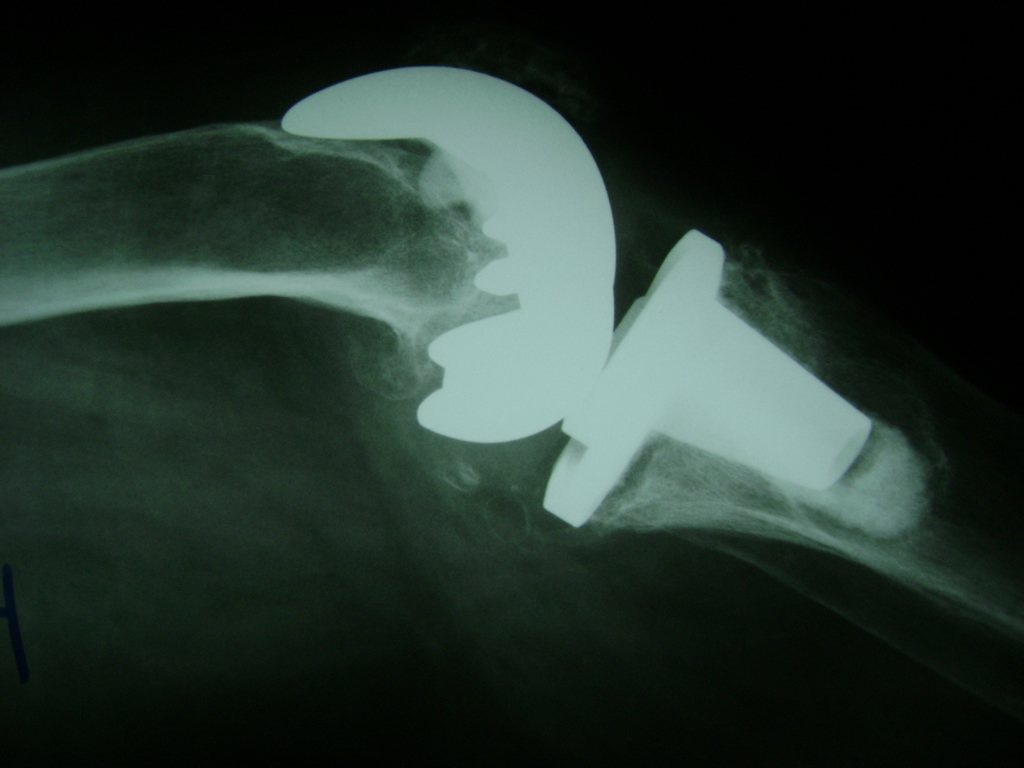

Cirugías de Calcaneo - Rodilla

La artroscopia de rodilla es un cirugía en el cual la estructura interna de la articulación es examinada ya sea para realizar un diagnostico o para realizar un tratamiento, este procedimiento se realiza utilizando un instrumento parecido a un pequeño tubo llamado artroscopio.